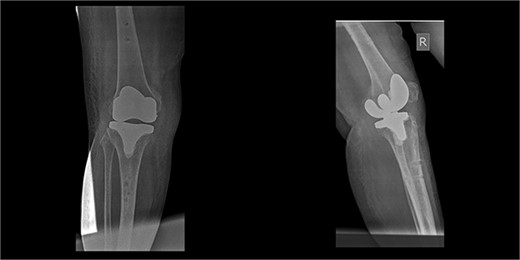

The patient underwent a medial-pivot design TKA (Evolution Medial-Pivot Knee System, Microport, China). Intraoperatively, a full ROM was achieved only after extensive soft tissue and bone releases. The extension gap was limited by significant hamstring spasticity, and a proper extension gap was attained after additional anterior femoral cut. Early postoperative recovery was uneventful (Fig. 2). On the third postoperative day, the patient complained of severe knee pain accompanied by excessive swelling during kinesiotherapy. Clinical examination showed a posterior sag sign at 30° of flexion (Fig. 3). No signs of neurovascular deficit were obvious. A knee X-ray revealed posterior TKA dislocation and a small, non-displaced femoral fracture (Fig. 4). The tibial component was reducible, but redislocation occurred with the knee extended over 90°, indicative of severe instability. Laboratory investigations, including erythrocyte sedimentation rate and C-reactive protein, were normal. A knee arthrocentesis was performed with no substantial findings. Two botulinum toxin injections (200 IU) to the hamstrings were performed without improvement. Local muscle hypertonia was evaluated through a neurological examination and a brain computed tomography scan, with no remarkable findings. The patient’s history included intramedullary nailing of the right femur due to an intertrochanteric fracture 8 months before the TKA.

The patient was reoperated, where a more extensive release of the hamstrings was performed, obtaining full extension. The knee was stabilized using a lateral external fixator (Fig. 5). Muscle biopsies were obtained, indicating signs of chronic inflammation. Full weight bearing, using a walker, was permitted from the first postoperative day without substantial complaints.

The external fixator was removed after 6 weeks (Fig. 6), and physical therapy was initiated. The patient’s postoperative course was uncomplicated. One week upon removal, 0°–80° of flexion was achieved through everyday kinesiotherapy. On her last visit, 1 year postoperatively, the patient was ambulatory, with knee ROM of 0°–100° (Fig. 7). No further abnormal neuromuscular signs were observed.